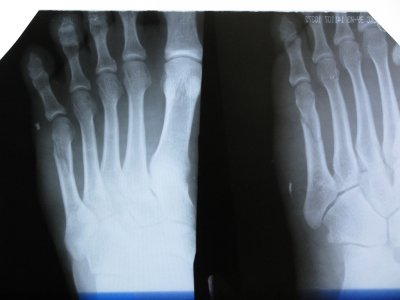

снимки ноги. 10 дней после перелома.